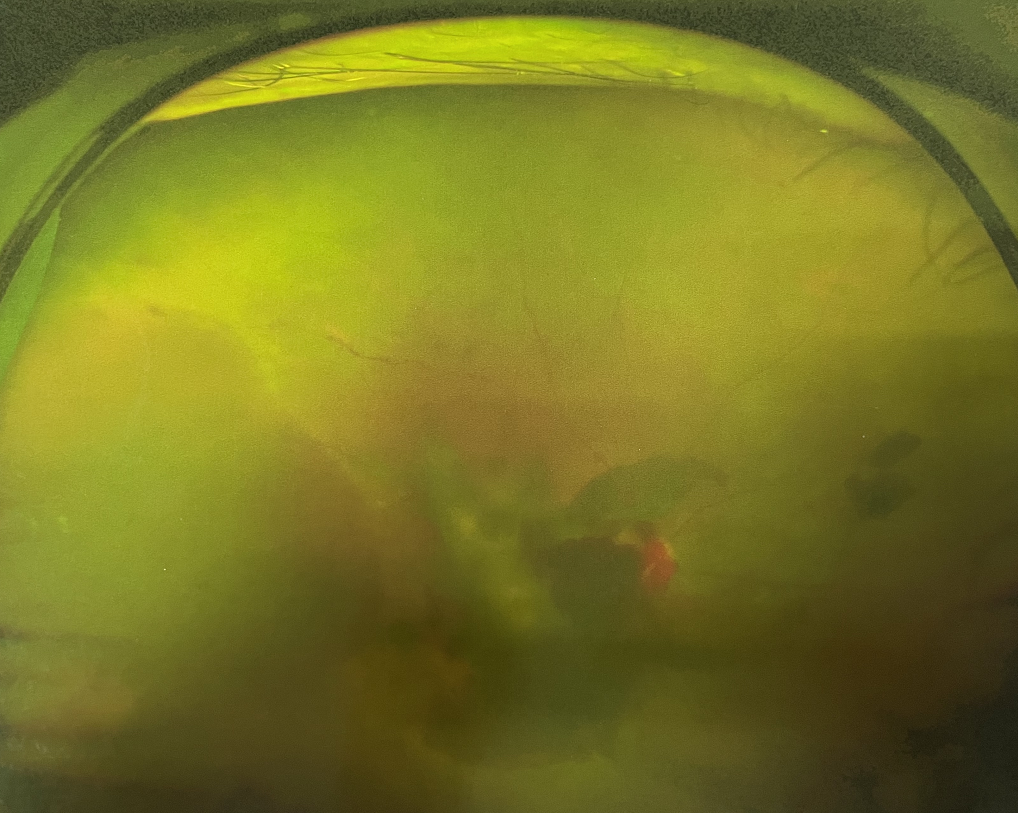

眼底出血不是獨立的眼病,而是由于眼球自己的病變和某些全身疾病的并發(fā)癥導致眼底的視網(wǎng)膜或脈絡膜出血,如果出血量大就會進入到眼球的玻璃體內(nèi),從而影響視力,如果沒有得到恰當?shù)闹委熆蓭砀鼑乐氐牟l(fā)癥造成失明。

眼底出血的患者,如果出血量少,而且在視網(wǎng)膜周邊部可能沒有明顯癥狀,患者僅感到眼前有黑影浮動;如出血量多,將嚴重影響視力,甚至完全被黑影所遮擋僅剩光感;如出血位于視網(wǎng)膜的黃斑區(qū),患者視野中心區(qū)被暗影遮擋,周邊尚有部分視力。

先是散瞳檢查眼底,可以明確眼底出血的性質(zhì),出血部位和出血量有多少。眼B超檢查,對于眼底出血量特別多,無法看清眼底的患者,就需要進行眼部B超檢查,以了解出血量,出血部位、有無合并視網(wǎng)膜脫離;還可以明確是否患有視網(wǎng)膜或脈絡膜的腫瘤。